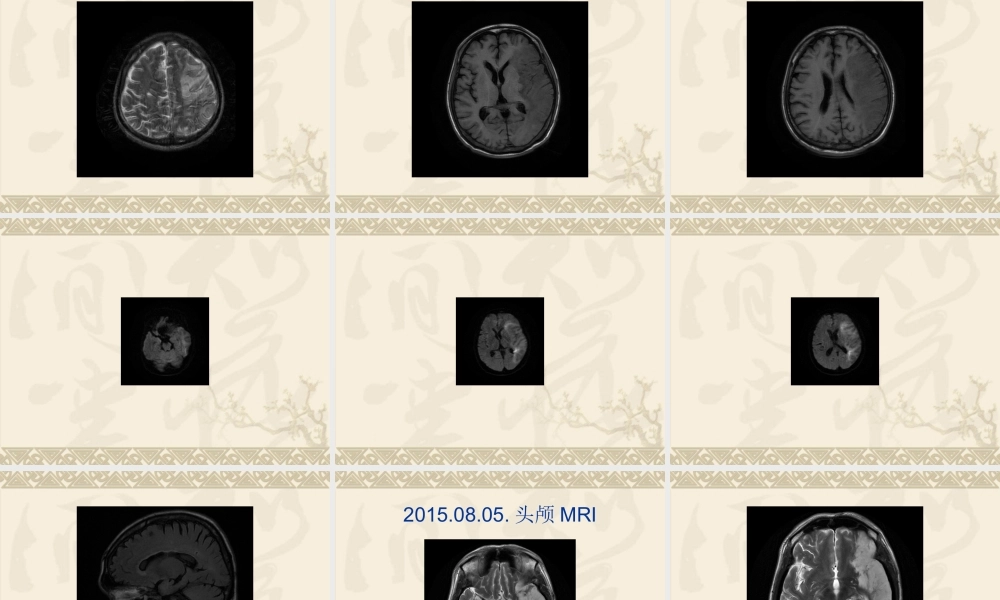

发热待查诊治思路探讨湖州市中心医院感染科童照威发热待查的定义:发热持续2周以上,体温超过38.5℃,经过完整的病史询问、体格检查以及常规的实验室检查,仍旧不能明确原因。发热的机理:各种病原微生物及其毒素、抗原抗体复合物、炎症或某些化学物质等外源性致热源,通过作用于体内细胞产生内源性致热因子,间接或直接作用于下丘脑体温调节中枢,使体温调节中枢的体温调定点水平升高,导致机体产热增加,而散热不能相应地随之增加或散热减少,使体温升高超过正常范围。发热待查病因的分类:感染性疾病(50%)非感染性疾病:1.结缔组织疾病(20%~30%)2.肿瘤性疾病(10%~20%)3.中枢性发热(脑溢血,酒精戒断综合征,)4.药物热5.功能性发热,伪装热不明原因占10%常见发热待查的原因:主要是感染性疾病细菌性心内膜炎败血症,包括导管相关败血症肺结核或肺外结核,如淋巴结结核,眼底、腰椎结核等。局部感染,腹腔感染,如盆腔脓肿,肝脓肿,腹部切口皮下脓肿颅内感染病例1患者,男性,在河南郑州打工。主诉:因反复发热2月入院。体温最高38.5摄氏度,无头痛,无咳嗽咳痰,无鼻塞流涕,无咽痛,无夜间盗汗,无恶心呕吐,无腹痛腹泻,无皮疹、关节肿痛,无尿频尿急尿痛,于外院间断输液治疗,具体诊治不详,体温无明显好转,既往史:既往体健,否认高血压病、糖尿病史,否认肝炎、结核病等其他传染性病史病例1查体:T:37.9,BP℃:135/74mmHg,P:92次/分,R:19次/分,浅表淋巴结未及肿大,躯干部可见少量出血点,压之褪色,皮肤巩膜无黄染,口唇无紫绀,气管居中,胸骨无压痛,两肺呼吸音粗,未闻及啰音,心率92次/分,律齐,可闻及II~III级收缩期吹风样杂音,腹平软,肝脾肋下未及,移动性浊音阴性,双下肢不肿。病例1辅助检查:2015.01.05本院门诊尿常规:潜血试验3+,蛋白2+;抗O+类风湿正常;血常规:WBC:10.7*10^9/L,NE%:88.1%,HGB:93g/l,PLT:209*10^9/L,CRP:89.6mg/l;血沉:42.0mm/h;肿瘤10项:SF:518ng/ml,其余无异常;肝肾功能:ABL:30.5g/l,其余无异常;电解质:K+:3.94mmol/l,NA+:126.1mmol/l。胸部CT平扫(CT638479):两侧胸腔积液伴两下肺膨胀不全,右肺中下叶及左肺下叶纤维增殖灶。上腹部B超(超声号:2157586):未见明显异常。心电图:左室高电压心脏彩超:左房、左室、右房增大二尖瓣前瓣赘生物,二尖瓣前瓣见回声稍强光团一枚,大小2.4*2.1*2.1(cm),二...